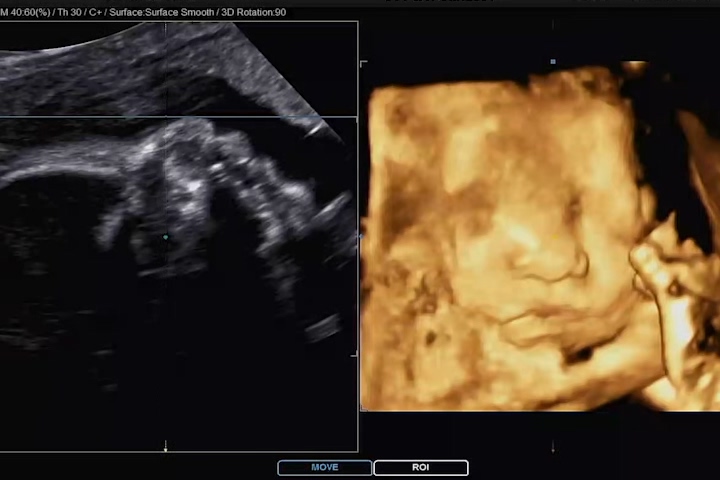

부모님과 함께 방문했던 어제가 마침, 까꿍이의 얼굴을 3D 초음파로 보여주는 날이었다. 우리 부모님 세대때는 아무래도 초음파 영상이 생소했기 때문에 꼭 한번 같이 방문하여 보여드리고 싶었다. 물론, 이 생각은 아내의 깊은 마음에서 시작된 것! 감사합니다😉😙

우리 부부와 부모님이 함께 들어간 초음파 검사실. 맨날 저장된 영상만 보여드렸었는데, 직접 담당 선생님이 설명해주면서 초음파를 보니 이해가 쏙쏙 되고, 까꿍이의 자세한 정보를 알 수 있어 굉장히 신기하고 즐거웠던 경험이었다고 부모님이 말씀하셨다.

우리 까꿍에 엄마 뱃속의 태반에 머리를 기대고 한쪽 손을 올리고 있어 깔끔하게 얼굴을 보지 못했지만, 나름 만족하게 얼굴을 볼 수 있었다. 사실 이번 초음파 사진 정도까지도 기대하지 않고, 코와 입술 살짝만 나왔으면 좋겠다 했건만 그 이상의 모습도 보여줬다.

잠을 자고 있는지 평소에 비해 움직임이 없던 까꿍이. 보통 3D 초음파는 눈을 감고 있기 때문에 눈 부분은 디테일하게 나오지 않는다고 하셨다. 그래도 영상 중간중간과 초음파 사진에는 눈 윤곽도 나와있어서 얼굴의 형태를 느낄 수 있었다.